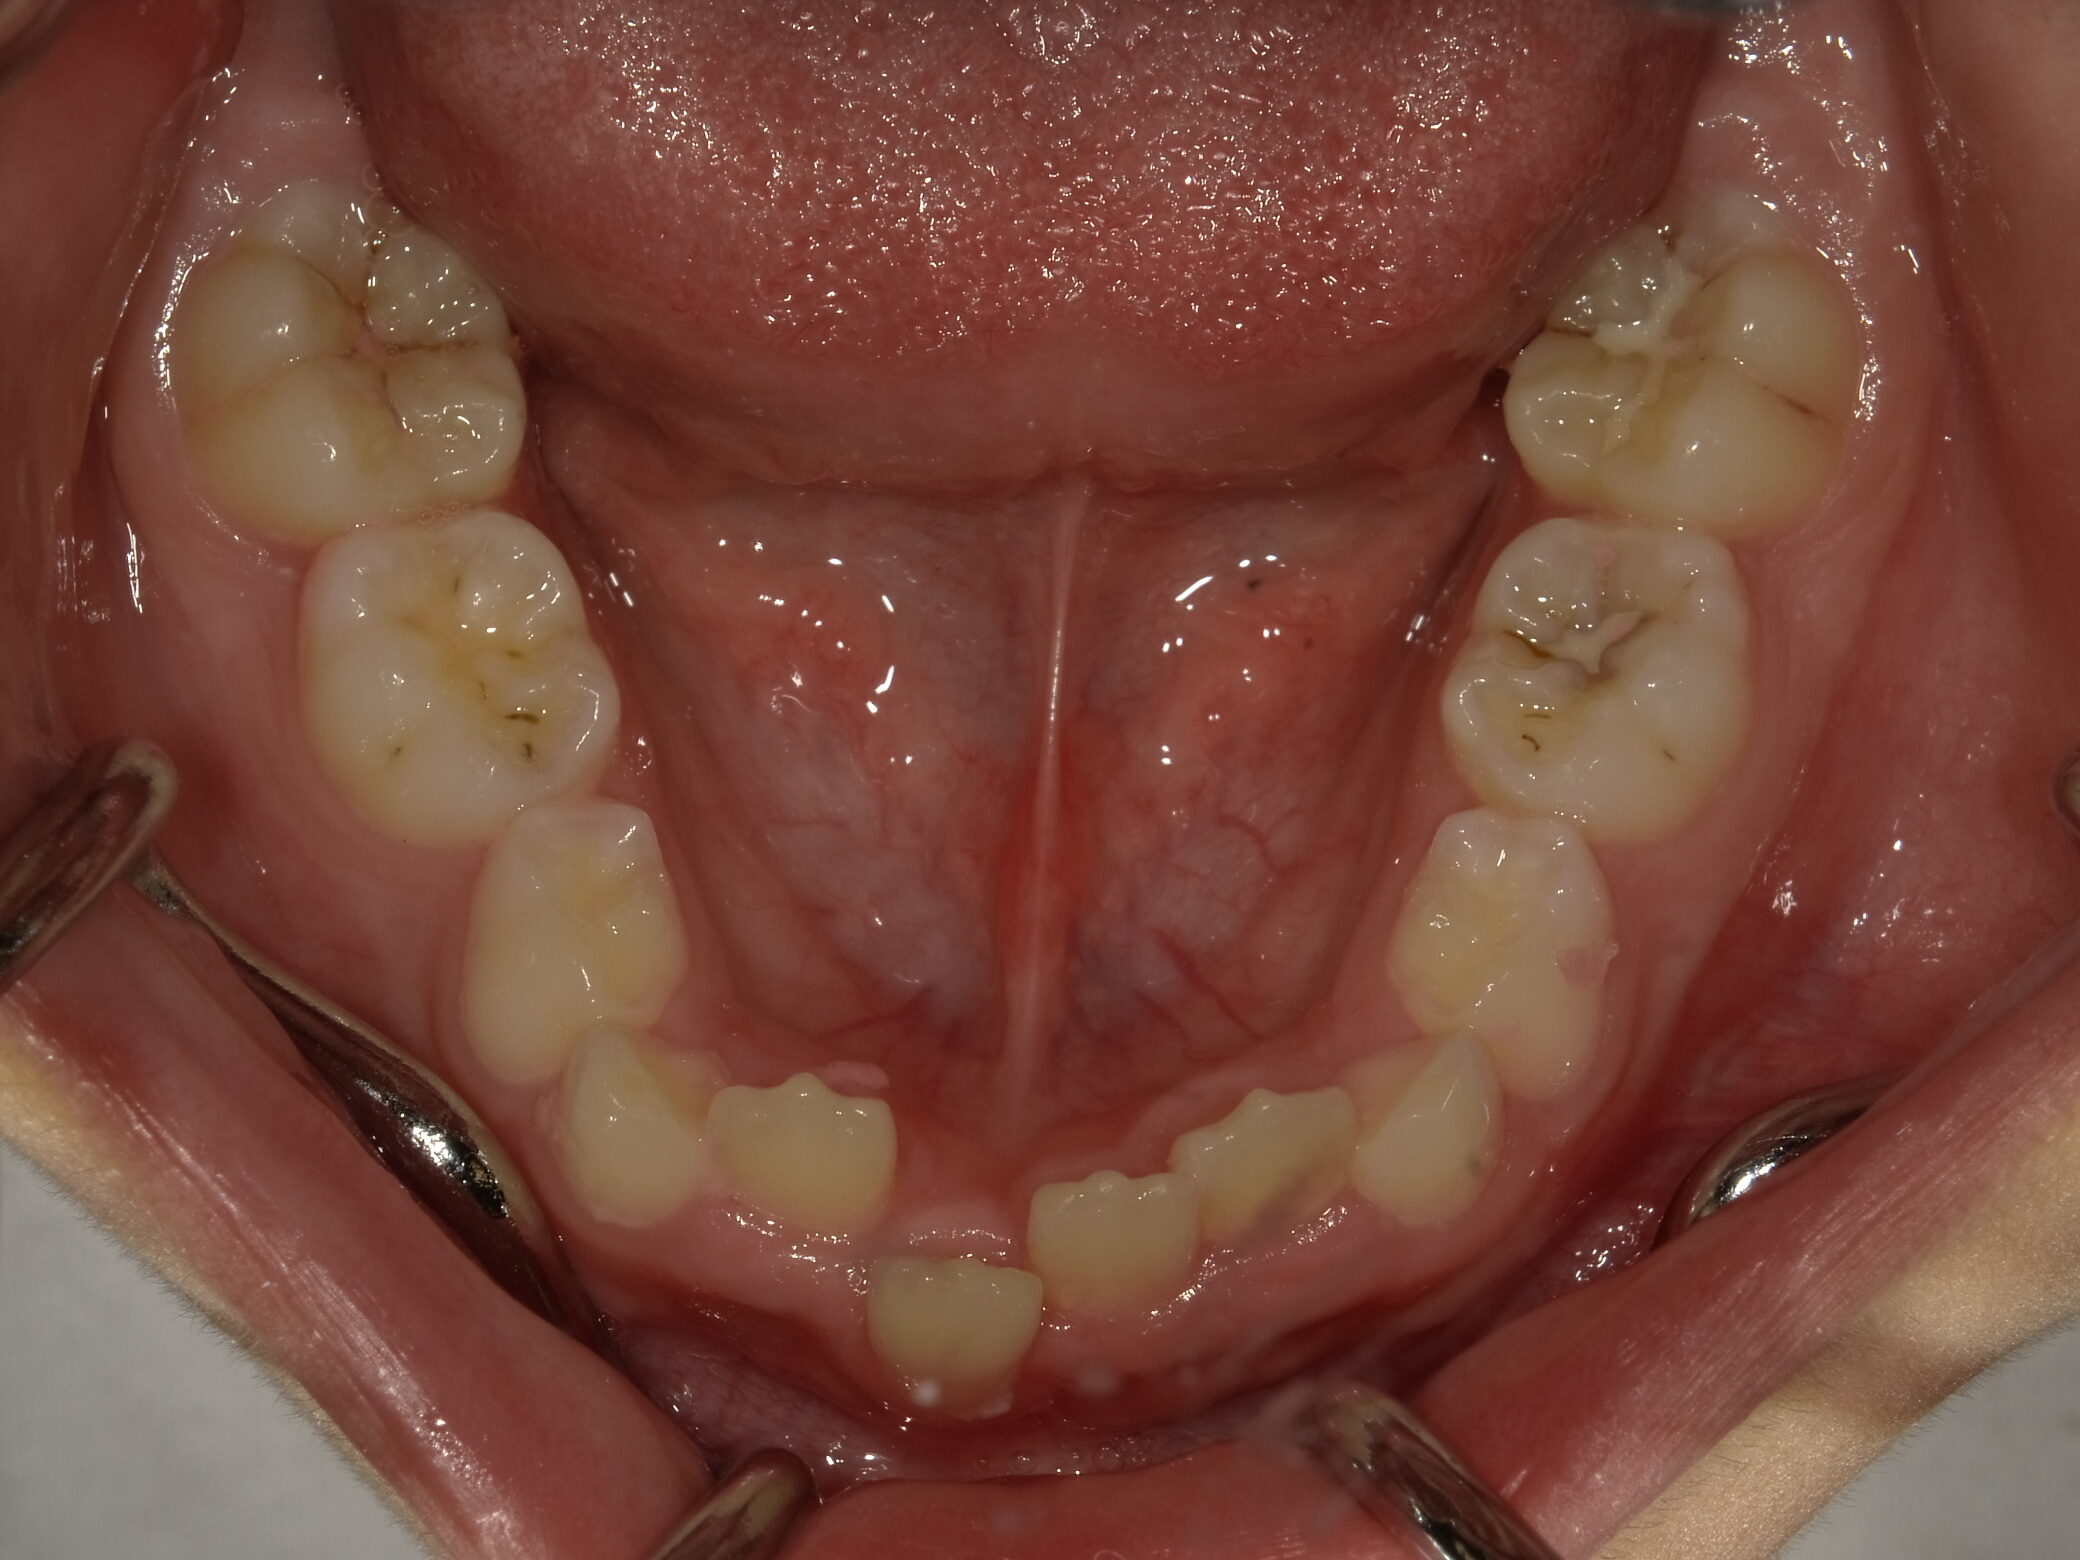

| 症例分類 | 交叉咬合 |

|---|---|

| 主訴 | 前歯がずれて咬んでいる |

| 年齢 | 9歳5ヶ月 |

| 性別 | 女性 |

| 抜歯部位 | なし |

| 使用装置 | 拡大装置、上顎前歯部のセクショナルアーチ装置、取り外し式保定装置 |

| 治療期間 | 1年2ヶ月 |

| 費用 | 相談料0円、検査料50,000円 動的矯正治療費330,000円 調整料6600円×15回分 保定装置料0円 |

| リスク・注意点 | 個々の歯の大きさに対して顎が小さく、歯が並ぶスペースが不足したために交叉咬合が生じています。これらを改善するために、幅の狭搾している歯列を側方に拡大した後、前歯を排列しました。

歯の動き方には個人差があり、予想された治療期間が延長する可能性があります。 治療中は矯正歯科装置が歯の表面に付いており、歯が磨きにくくなるため、むし歯や歯周病が生じるリスクが高まります。ハミガキを適切に行ってお口の中を常に清潔に保ち、さらに、かかりつけ歯科医に定期的に受診することが大切です。 矯正歯科装置の使用状況、定期的な通院など、矯正歯科治療には患者さんの協力が必要であり、それらが治療結果や治療期間に影響します。 治療の経過によっては当初予定していた治療計画を変更する可能性があります。 保定装置の装着時間が十分確保できない場合、歯並びや、咬み合せの「後戻り」が生じる可能性があります。 上下両側第二大臼歯の萌出を観察する必要があります。 |